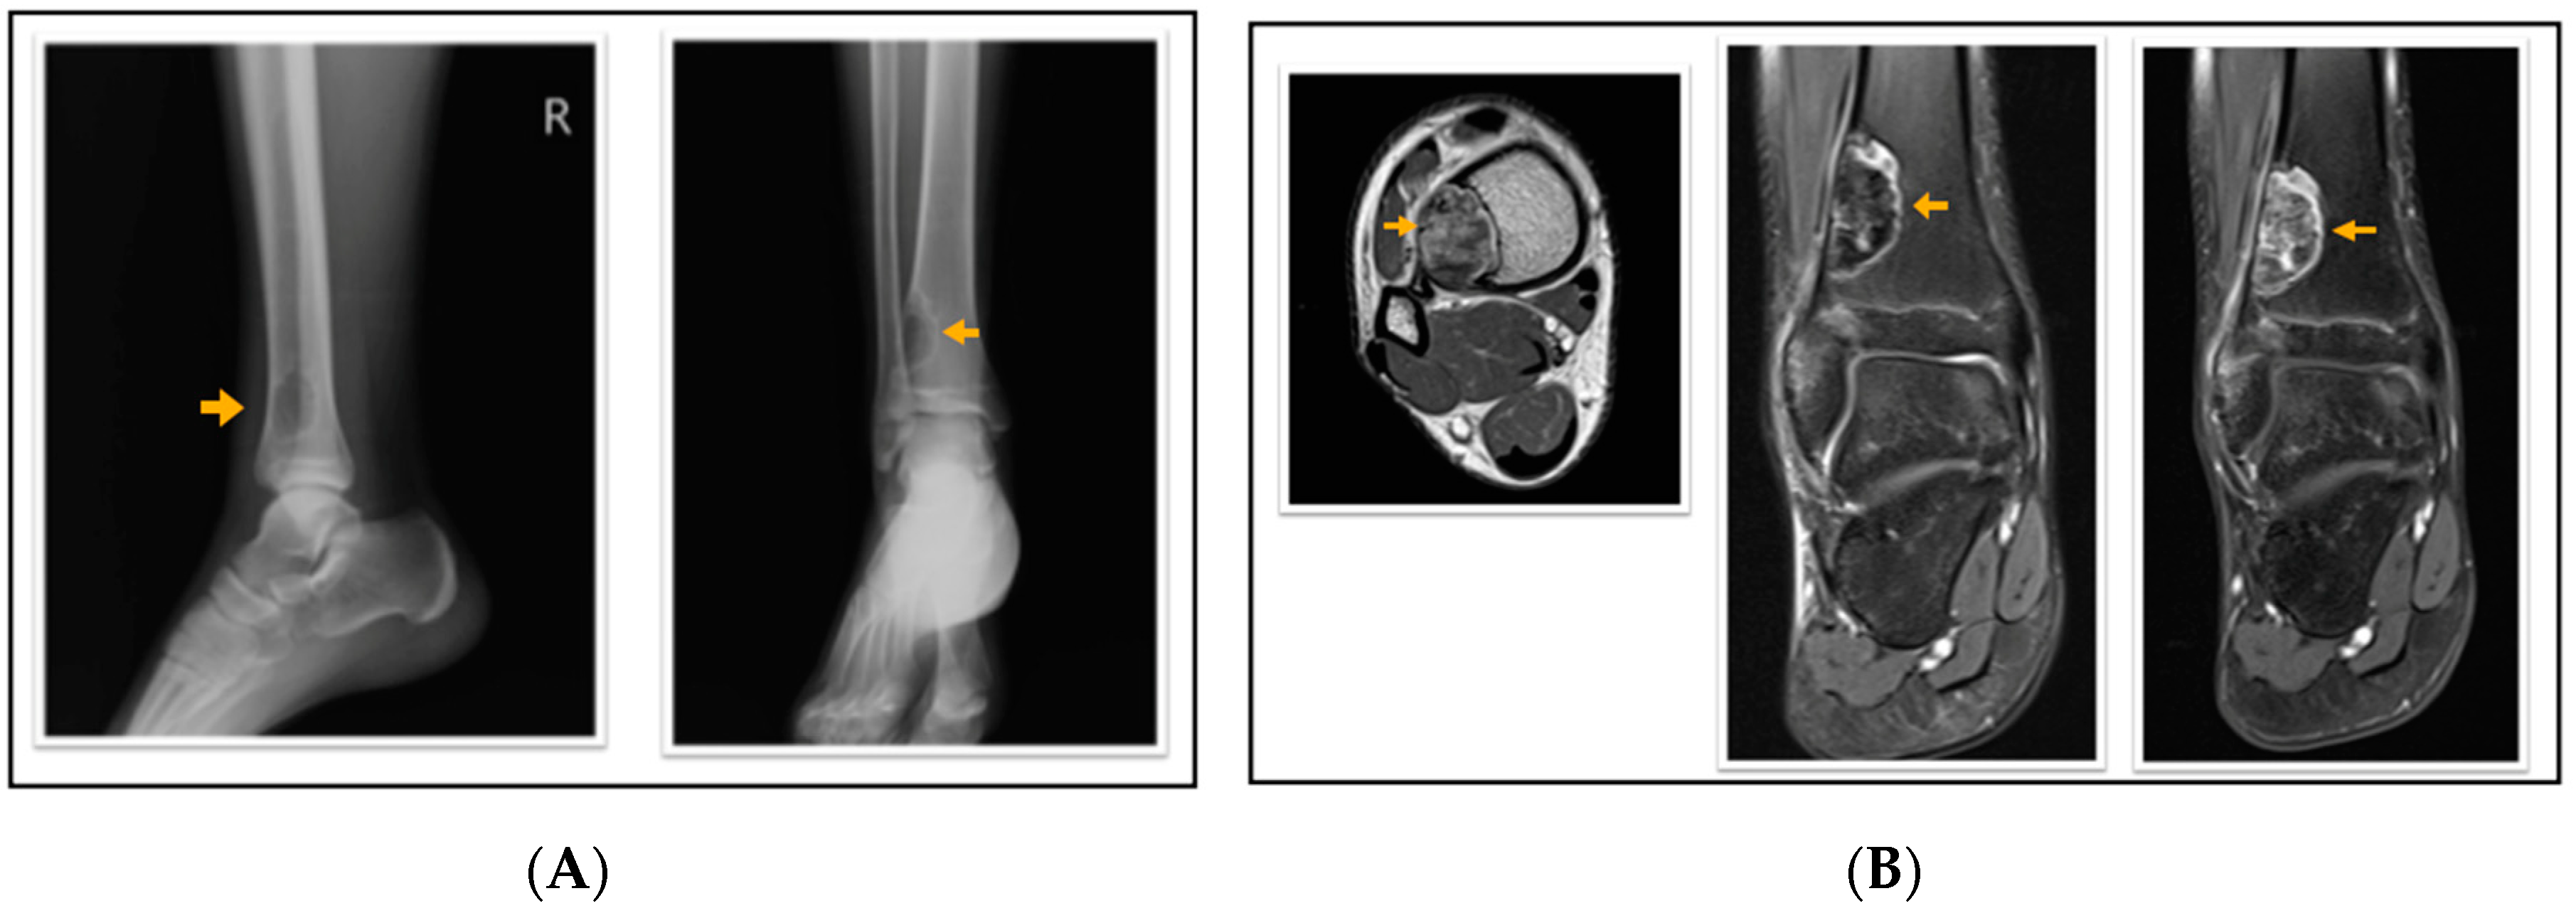

According to the radiological evaluation results, 34 lesions had X-ray scans available in the archive of the hospital. One of the patients had 3 lesions, and 2 patients had 2 lesions, while the rest had only 1 lesion, summarized as 34 lesions in 28 patients. All lesions were eccentrically located within the metaphysis of a long bone such that 22 lesions were in the femur and 12 lesions were in the tibia, 18 of the lesions were on the left side (Figure 1, Figure 2 and Figure 3). Only 4 lesions were examined with contrast-enhanced MRI; from these 3 had peripheral and only 1 had heterogeneous contrast enhancement after intravenous contrast media injection (Figure 1, Figure 2 and Figure 3).

Figure 2.

A 16-year-old patient with a fibrous cortical defect in the ankle. (A) Lateral and anteroposterior direct X-ray of a 16-year-old patient shows a lytic lesion with a sclerotic rim in the distal medial metaphysis of the tibia consistent with FCD. (B) Axial T1 weighted, coronal proton density, and coronal contrast-enhanced fat-saturated T1 weighted magnetic resonance images show sclerotic, non-contrast enhancing areas within the lesion. This lesion was classified as stage C according to Ritschl’s classification. Clinically, IPAQ (International Physical Activity Questionnaire):Inactive, Screen Time: 4 h, 21-Numbered Circle VAS (21-VAS): 3, VAS (Visual analogue scale): 3, 21-Numbered Circle Activity Scale (21-NCAS): 5.